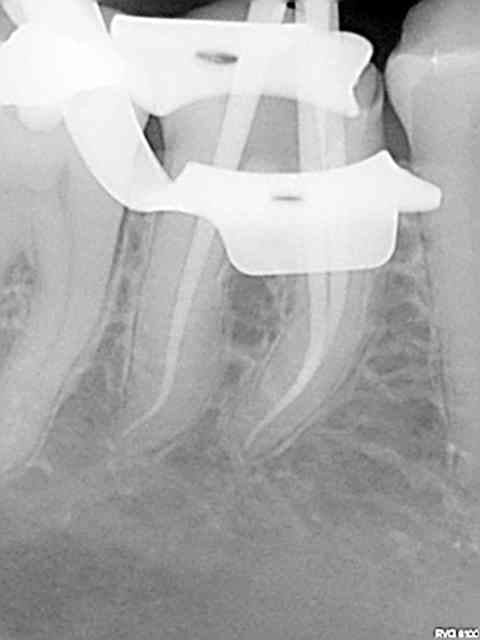

Et une de plus !

R19 vxiysf - Eugenol

R20 kboz6l - Eugenol

01 ukhwbq - Eugenol

C'est pas de la frime hein, mais ca fait plaisir d'avoir trouvé ENFIN une technique rapide et reproductible sans casse. (enfin presque il y a dans le tas un micro morceau de R25 pas loin de l'apex )